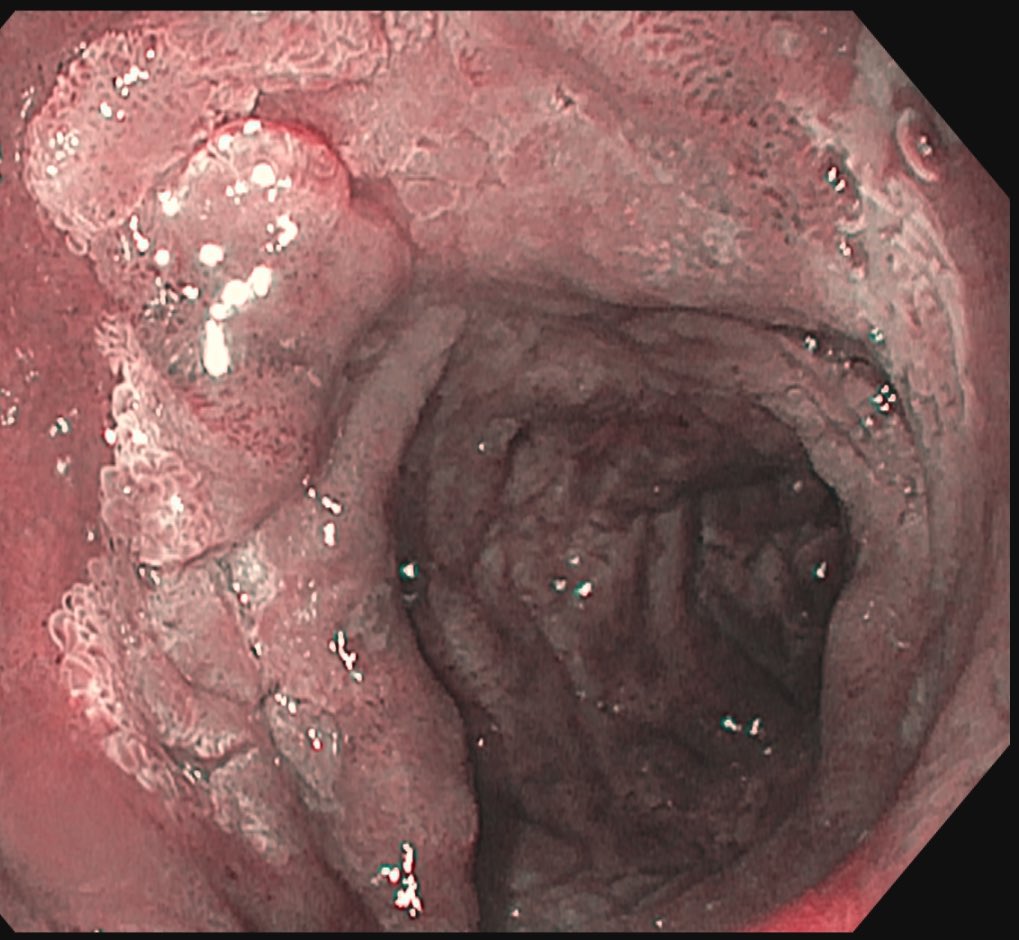

43-year-old fitness influencer ignored her GI symptoms for a year. Then she was diagnosed with stage 4 colon cancer: ‘It could happen to anyone’ fortune.com/well/article/c…